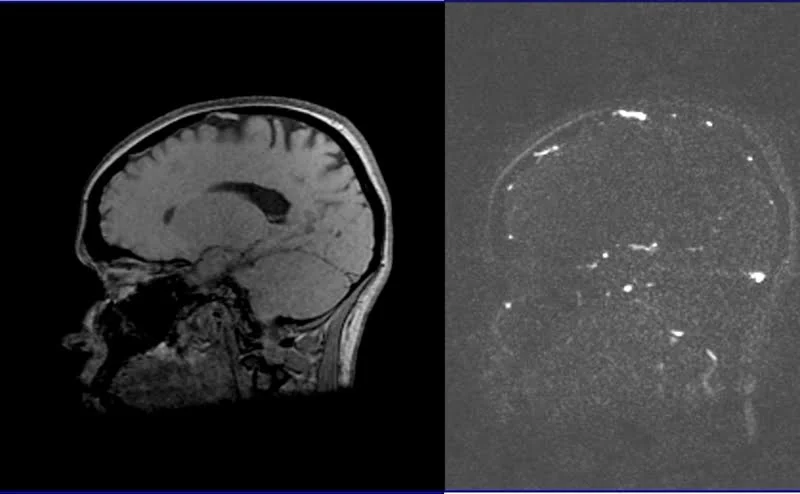

3D PHASE CONTRAST( PC) SEQUENCE USED IN MRV BRAIN IMAGING

POST PROCESSED MIP IMAGES